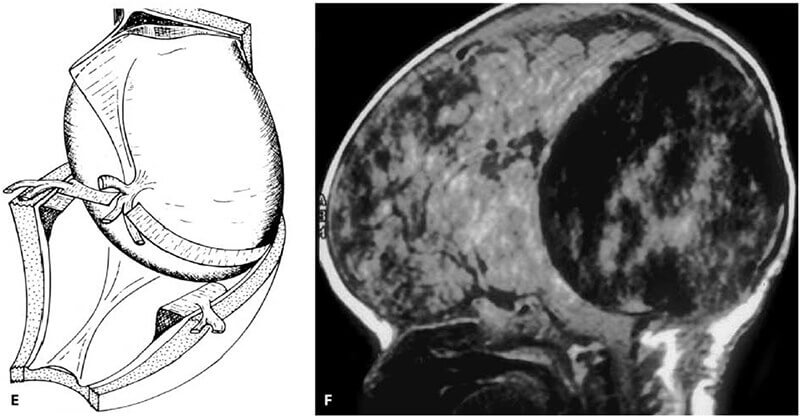

- Καθ´ αυτή δυσπλασία του φλεβώδους κόλπου (Dural Sinus Malformation, DSM) στα νεογνά, στην οποία οι αρτηριοφλεβώδεις επικοινωνίες στο τοίχωμα του φλεβώδους κόλπου είναι αποτέλεσμα της δυσπλασίας του φλεβώδους κόλπου.